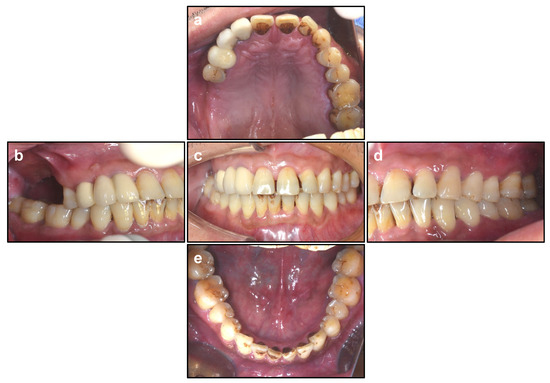

Figure 1.

Occlusal Relationship. (a) Maxillary. (b) Right. (c) Occlusal. (d) Left. (e) Mandibular.